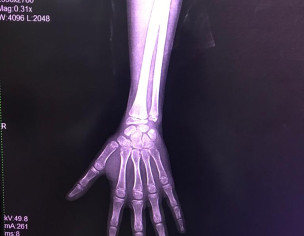

Asking for Sister, Female, 13 years old, Multan

Meri sister ki age almost 13 years ha but us ki height almost 7/8Y ki lgti ha ... Height k liay koi achi medication bta dein kindly . Us k test bhi krway hain or x-ray bhi . Sb thk ha alhumdulillah but height nahi barh rahi

Attach Photo here: